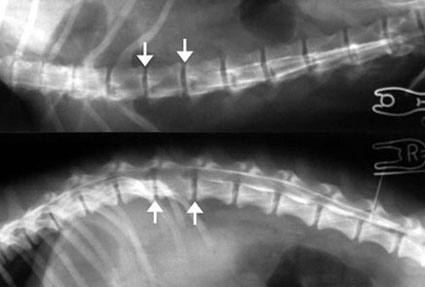

ハンセンI 型の椎間板ヘルニア症の症例

4歳齢、体重5kgのミニチュア・ダックスフント。

3日まえから痛みをうったえる様子があり、1日前からは後駆麻痺状態となり内科治療をしたが改善しなかったとのことで、主治医から脊髄造影と片側椎弓切除手術(ヘミラミネクトミー)を依頼されました。

第13胸椎−第1腰椎間と第1−第2腰椎間の特に右側で、脊髄圧迫が認められましたので、同部位右側からのヘミラミネクトミーを実施しました。

写真上段: 脊髄造影X線写真

上半分は腹背像、下半分は側面像。白矢印で示した部位で造影剤の白いラインが消えており、脊髄が圧迫されているのがわかります。